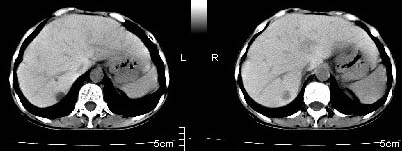

ct:肝胃之间、胰头后、腹主a周围,融合而成团块状影,包绕血管,胰腺前移后缘分界欠清,与肝胃分界清,肿块未见明显强化,肝右叶后段小囊肿。

肝胃之间、胰头后、腹主a周围,融合而成团块状影,包绕血管,胰腺前移后缘分界欠清,与肝胃分界清,肿块未见明显强化,考虑淋巴瘤可能性大

肝胃之间、肝十二指肠韧带,胰头后、腹主a周围,融合而成团块状影,包绕血管[腹腔干、肠系膜上动脉,腹主动脉],胰腺前移后缘分界欠清,与肝胃分界清,肿块未见明显强化,肝右叶后段小囊肿。

主动脉-胰腺间隙可见巨大分叶状软组织肿块影,包绕腹主动脉、腹腔干及其分支、腔静脉等大血管,增强呈无明显强化,临近脏器明显受压移位,增强示有分界。肝右叶可见局限性低密影,边缘清楚。

考虑腹膜后淋巴瘤。

影象表现:平扫,首先可见胃壁明显增厚,内外边缘清晰,外缘光滑,内边缘不归整,同时胃腔明显缩小。

再看从肠系膜根部到胰腺后主动脉及上腔静脉周围可见相连的较大的软组织肿块影,形态不规则,呈明显

的大小不等的分叶状,其中密度较均匀但其中可见条状低密度区,肿块边缘比较清晰周围的小肠受压移位

明显且堆积。

增强所见,腹腔动脉,肠系膜上动静脉被肿块包绕,结合平扫的条状低密度区恰好位于血管周围,较大的

肿块强化不明显(遗憾的是没有标上ct值)但胃壁强化的十分明显。